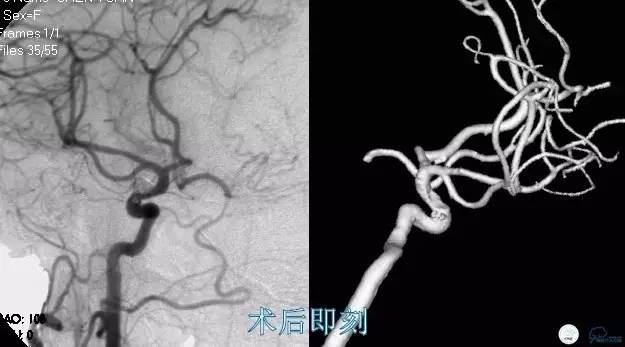

Case2 左ICA床突旁动脉瘤术后稳定

术前VS术后即刻